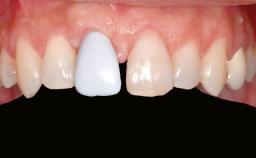

Patient's Esthetic Expectations Low Medium High

Lip Line No exposure of papillae Exposure of papillae Full exposure of mucosa margin

Shape of Tooth Crowns Rectangular Triangular

Esthetic Risk High